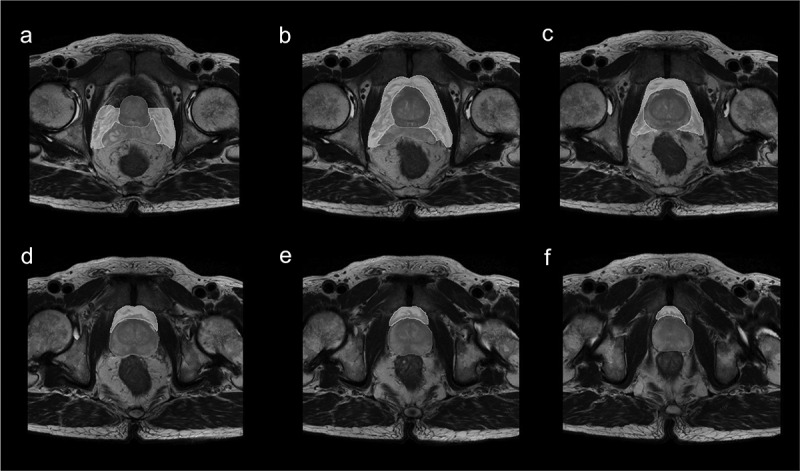

Methods: A retrospective study of 151 PCa patients (October 2010-November 2022) was conducted. Radiomic features were extracted from axial T2-weighted MRI of PPAT, and normalized PPAT was calculated as the ratio of PPAT volume to prostate volume. A radiomics score (Radscore) was developed using logistic regression with 16 features selected via LASSO regression. Independent predictors identified through univariate and multivariate logistic regression were used to construct a nomogram. Predictive performance was assessed using ROC curves, and internal validation involved 1000 bootstrapped iterations.

Abstract Image